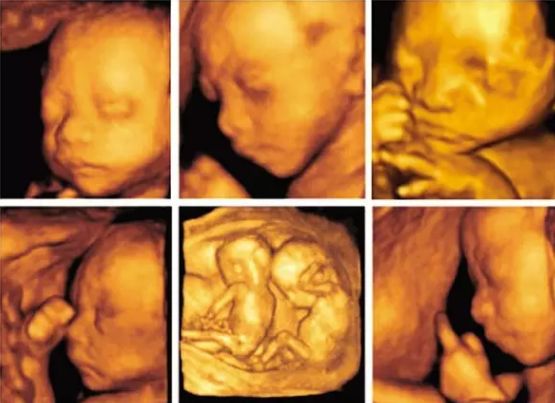

而要查出唇面部的问题是四维彩超,四维彩超,是把不同时间的3D超声图像连成动图,实时的看到宝宝的动态活动,观察运动神经系统是否正常,运动是否协调。

四维彩超可以看手脚、面部五官、心脑有无异常,能显示出某些先天缺陷,比如唇腭裂。

如果准妈妈照的是四维彩超,还可以看到宝宝的实时面部表情呢。